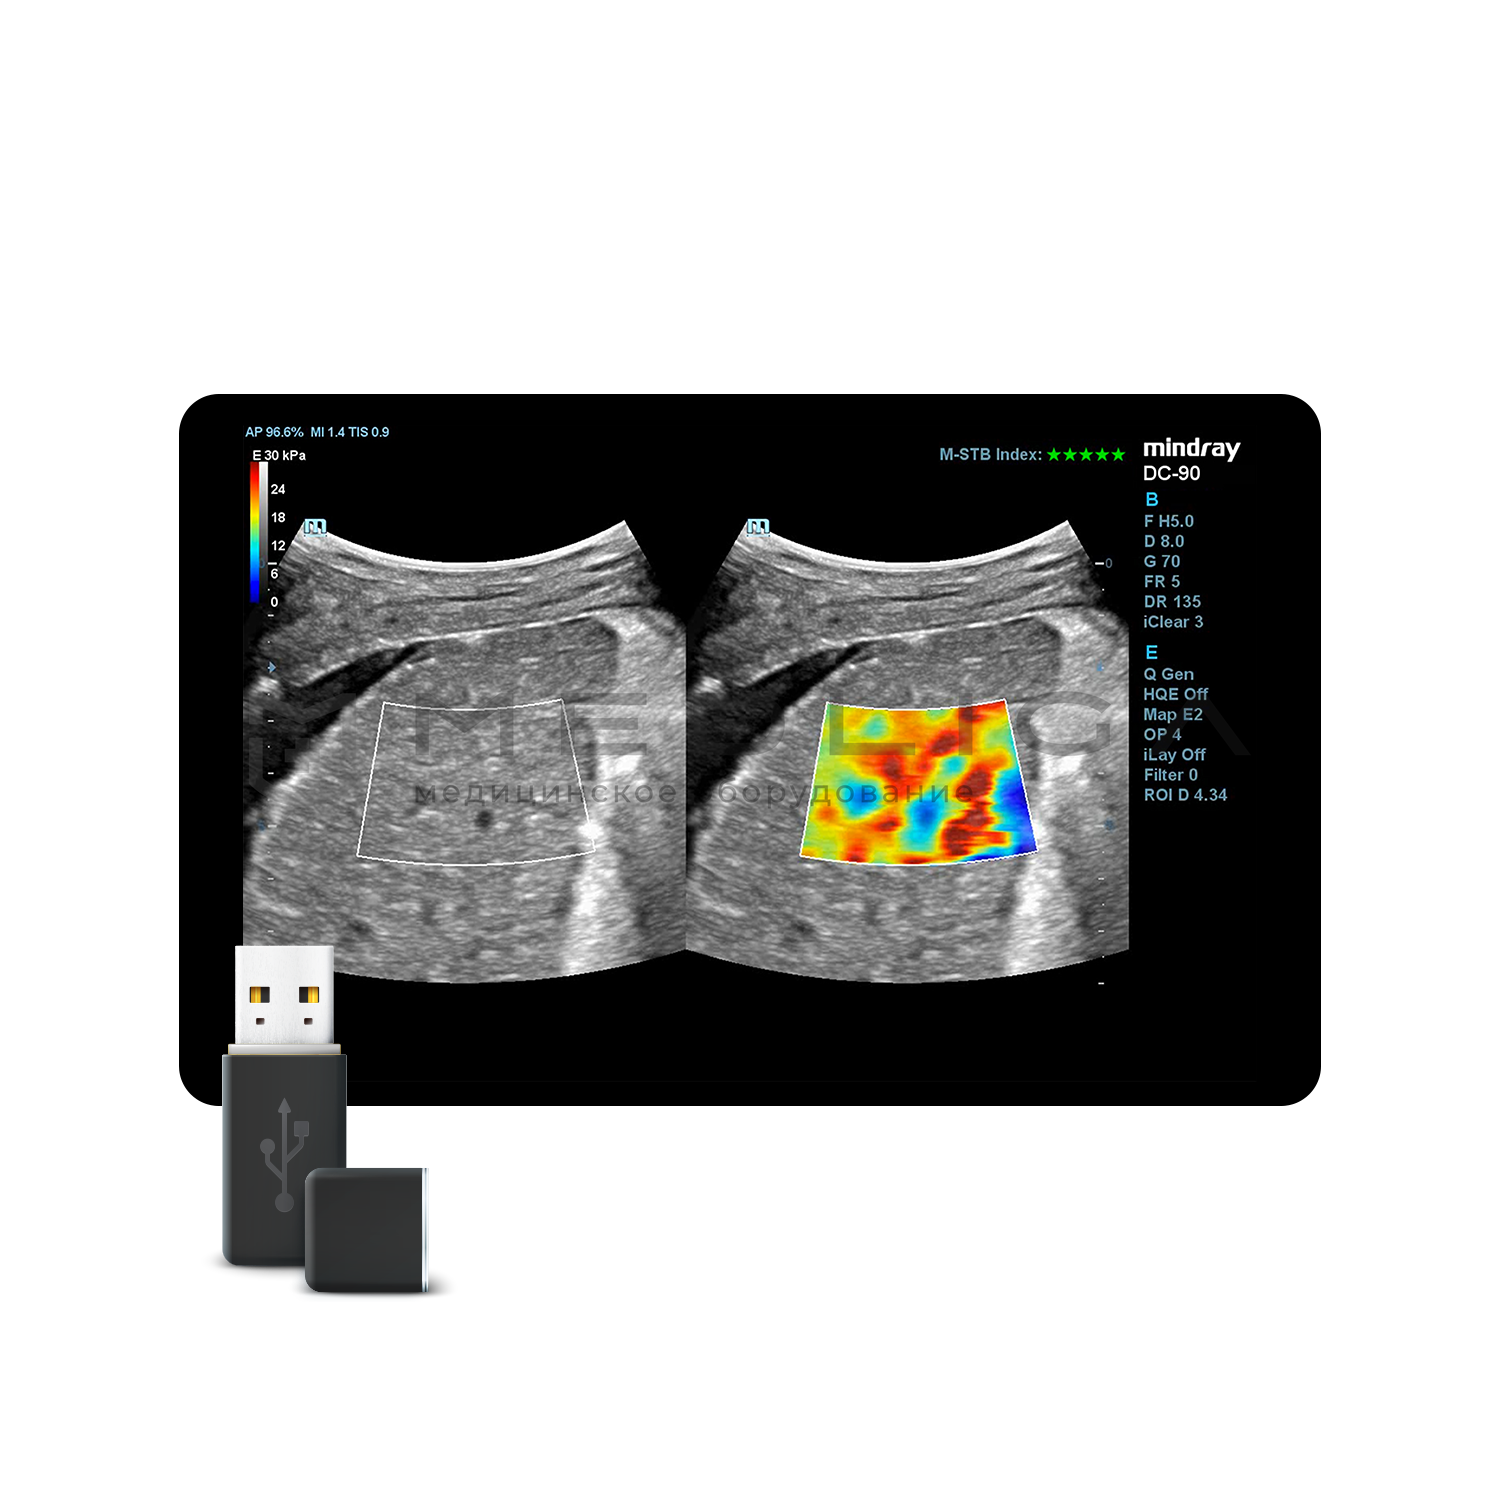

STE (Sound Touch Elastography)

STE интегрирована с эксклюзивной технологией Ultra-Wide Beam Tracking от Mindray для двумерной эластографии сдвиговой волной в реальном времени. Специализированные измерительные инструменты позволяют проводить количественный анализ модуля упругости с высокой точностью.